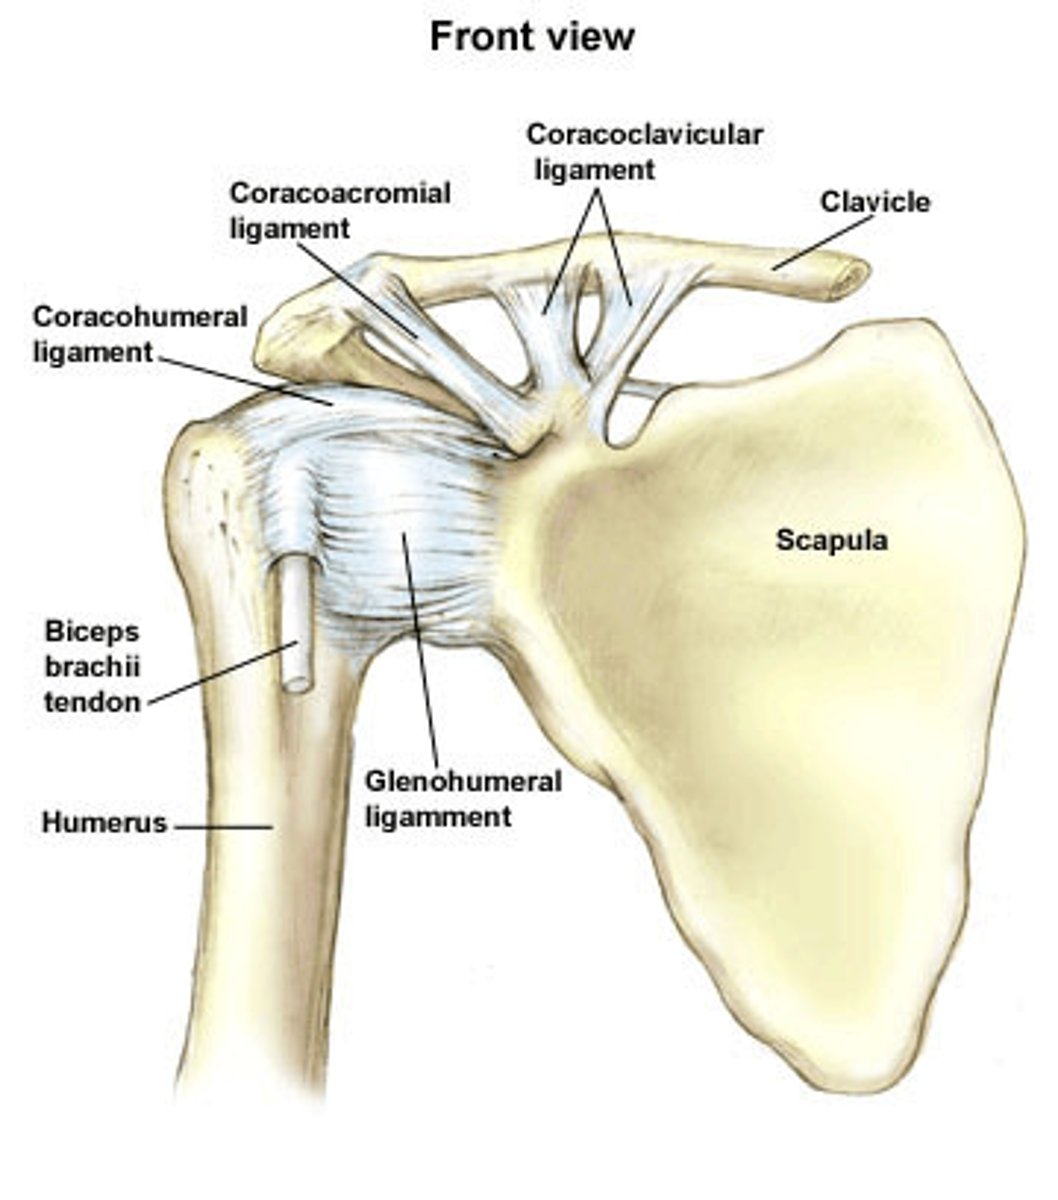

Location of conoid tubercle of the inferior surface of the clavicle:

near acromial end of clavicle

Function of conoid tubercle on the inferior surface of the clavicle:

support for the medial part of the coracoclavicular ligament

Location of the trapezoid line of the inferior surface of the clavicle:

nearer to the acromial end than the conoid tubercle

Function of the trapezoid line of the inferior surface of the clavicle:

support for the lateral part of the coracoclavicular joint

Glenoid cavity of the scapula:

- on the lateral surface of the scapula

- located superolaterally receives and articulates with the head of the humerus (glenohumeral joint)

What is the name of the joint between the glenoid cavity and the head of the humerus?

the glenohumeral joint

Coracoid process of scapula:

- on lateral surface of the scapula

- superior to the glenoid cavity, projects anterolaterally